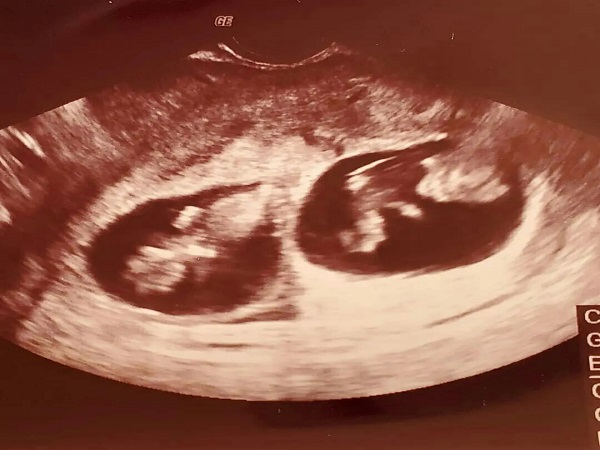

现在大多数不孕不育的家庭都会选择通过试管婴儿技术来实现生育的目的,有的家庭是想要拥有一对双胞胎,而有的家庭则只想要一个孩子。其实,试管婴儿移植的时候医生都会移植1-2个胚胎到女性的子宫内,这样主要是为了进一步提高试管婴儿的成功率。如果是两个胚胎都发育成了胎儿那么就是双胞,如果只有一个发育成了胎儿就是单胎,但是到底是单胎还是双胎就不一定了。

1试管婴儿单胎:试管婴儿单胎其实就是移植1-2个胚胎之后,其中一个胚胎最终着床在了女性的子宫内膜上并发育形成了胎儿。一般来说,试管婴儿单胎的成功率就和普通的试管成功率差不多,大概就是40%-50%左右;2试管婴儿双胎:试管婴儿双胎就是移植的2个胚胎均成功着床并发育形成了胎儿,出现这种情况的几率相对来书是比较小的,成功率大概在20%-30%左右,而且试管婴儿双胎的风险性比较高,所以大家要谨慎考虑是否减胎。